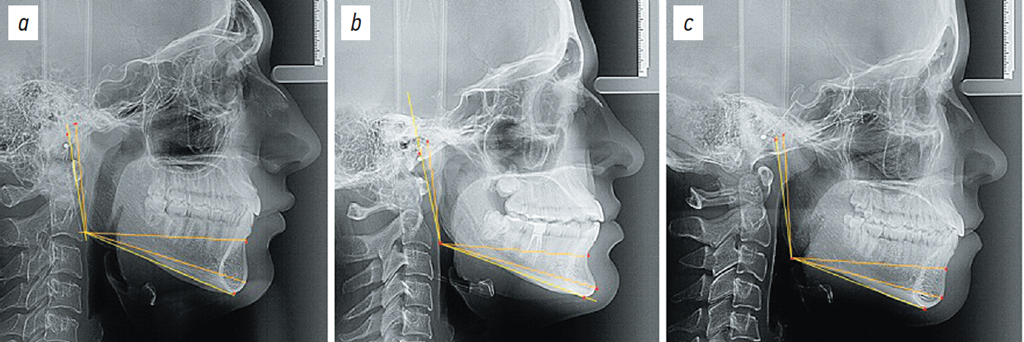

На фотографии телерентгенограмм наносили точки, применяемые в клинической практике ортодонтии. На суставном отростке нижней челюсти в верхней его точке ставили точку кондилион (Сond) а наиболее выпуклую точку задней его поверхности обозначали как Со. В области угла нижней челюсти на задней выпуклости ветви ставили точку Т1, а на нижней выпуклости угла на теле челюсти ставили точку Т2. Нижняя точка подбородка (Ме) при соединении с точкой Т2 определяла положение мандибулярной линии. Выпуклости ветви позволяли провести к ней касательную линию Со-Т1. Место соединения проведенных касательных линий — конструктивная точка гонион (Go), служившая отправным ориентиром для измерения высоты ветви (Gо-Сond) и длины тела нижней челюсти. Длину тела измеряли между разными ориентирами, в частности до точки ментос (Gо-Ме), до наиболее выступающей точки подбородка погонион (Gо-Pog) и до cупраментальной точки Downs (Gо-B(SM)) (рис. 1).

Рис. 1. Положение точечных (а) и линейных (b) ориентиров для определения размеров нижней челюсти.

Fig. 1. Location of cephalometric landmarks (a) and linear measurements (b) used to determine mandibular dimensions.

Также определяли отношение длины тела к высоте ветви нижней челюсти: длину подбородочного выступа оценивали через разницу между размерами линий Gо-Pog и Gо-B(SM).